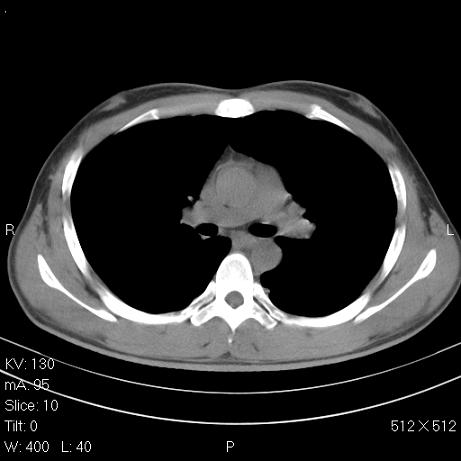

标题: CT7171B:补充治疗后2周复查

治疗后2周复查,请讨论

结合以前的ct片,还是考虑肺挫伤,吸收多了。

支持:创伤性湿肺。现肺挫裂伤(出血 积气)大部分吸收。建议继续治疗!

支持:创伤性湿肺、肺挫裂伤。现肺挫裂伤(出血、渗出、液气腔)大部分吸收。建议继续治疗!

经治疗后病灶明显吸收,考虑创伤性湿肺、肺挫裂伤